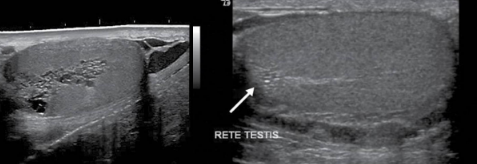

the seminiferous tubules converge at the ________ of each lobule and anastomose to form ________________

apex, rete testis

mediastinum

where all the tubules join together at rete testes

mediastinum testis

posterior aspect of tunica albuginea that forms vertical septum

tubular ectasia of rete testis

uncommon benign condition with cystic dilation and formation of cysts within the rete testis

associated with spermatocele, epididymal, or testicular cyst